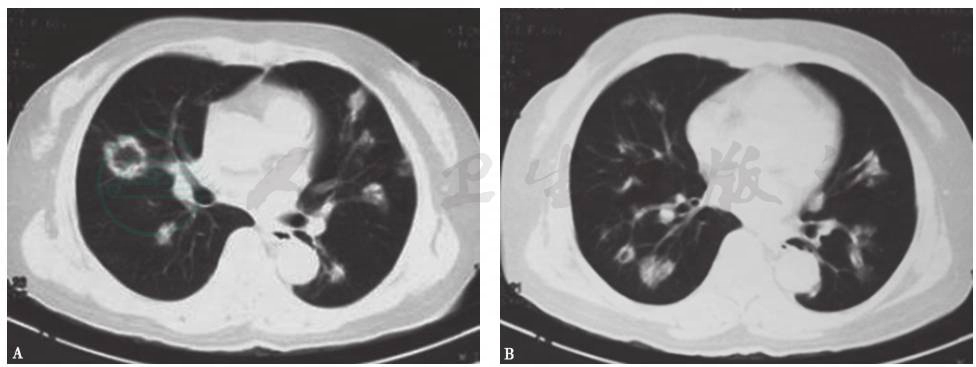

发病第32天,患者转至当地上级医院就诊,胸部CT提示病变较前加重,可见双肺多发大小不一的结节影,部分呈反晕环状,边缘尚清(图2)。

图2 发病第32天胸部CT表现